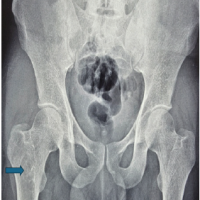

A 23-year-old male with no known comorbidities presented with complaints of pain, swelling, and instability over the right knee following twisting injury while playing football 3 years back. On examination of the knee, there was no healed scar suggestive of any external injury. There was minimal swelling of the right knee and varicose veins all over the right lower limb. The right lower limb was found to be 1 cm longer than the left, accounted by 0.5 cm in the femur and 0.5 cm in tibia. The bulk of the thigh and leg was larger by 1.5 cm on the right side compared to the left side (Fig. 1 is self-explanatory). There was a port-wine stain over the lateral aspect of the right thigh (Fig. 2). He did not have any features suggestive of ligamentous laxity. The knee range of movement was full. Posterior sag sign was present. The posterior drawer test was positive. Varus and Valgus stress tests were negative. The McMurray test for both menisci was negative. Dial test and pivot shift test were negative. Tests for ACL insufficiency were negative. X-ray standing anterior–posterior (Fig. 3), 45° flexion, weight bearing, and merchant patellar views were taken with contralateral view for comparison. This showed a positive sag compared to the contralateral knee.

Magnetic resonance imaging of the right knee was taken, which showed altered marrow edema within both condyles of femur and tibia, suggestive of marrow contusion. Complete rupture of PCL (Fig. 4) and focal radial tear of the posterior horn of medial meniscus at the periphery. Also showed a moderate knee joint effusion with a small Baker’s cyst. Doppler study of the right lower limb was done, which showed multiple incompetent perforators in the leg. There was no evidence of deep vein thrombosis. An ultrasound study of the abdomen was done to rule out abnormalities in the abdomen or pelvis. Systemic examination of the cardiovascular system and other systems did not reveal any abnormalities. Based on the clinical triad, diagnosis of KTS was made.